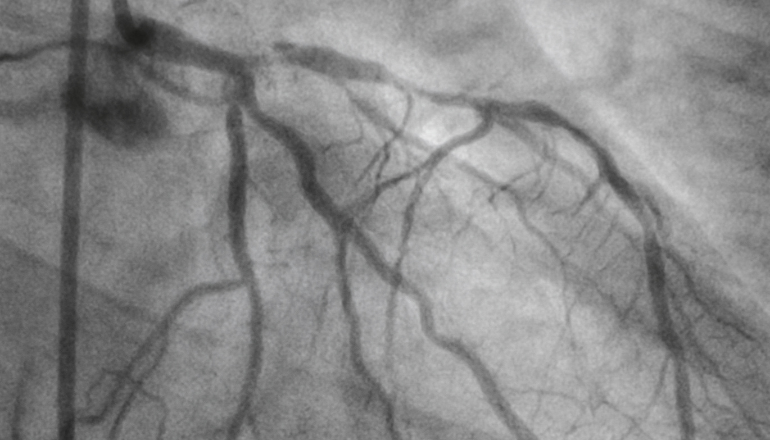

Cardiovascular Disease (CVD) is responsible for one in ten deaths in Australia. Early identification of those at risk of CVD is the cornerstone of General Practice. The use of Calcium scores and CT scans remains a vital role in risk stratification in the community.

Join Dr Mean Salib, Interventional Cardiologist as he reviews important infmoration related to the use of this tool, reviewing outcomes and when to refer for definitive treatment. Dr Salib will also share techniques used when treating these patients once they are referred for investigation.Review the role of Calcium scores when identifying those at risk of Coronary Artery Disease (CAD)